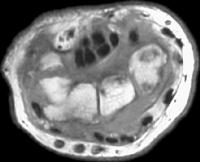

MRI revealed poorly defined soft tissue prominence deep to the extensor tendons and small cystic carpal changes.